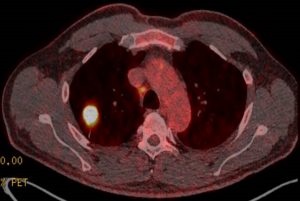

Das Behandlungsspektrum der Thorakalen Onkologie umfasst neben bösartigen Erkrankungen der Lunge sowie der Atemwege u.a. auch Tumore der Pleura und des Mediastinums. In den letzten Jahren sind insbesondere in diesem Bereich viele technische Fortschritte erzielt worden. Diagnostisch werden beispielsweise Untersuchungstechniken wie der endobronchiale Ultraschall zur minimal-invasiven Diagnosestellung oder neueste Methoden der molekularen Gewebediagnostik eingesetzt. Die gewonnenen Erkenntnisse tragen dazu bei im Rahmen von interdisziplinären Tumorkonferenzen unter Berücksichtigung des individuellen Patienten Therapieentscheidungen zu treffen. In Abhängigkeit des Tumorstadiums und des Gewebetyps stehen für die Patienten der Thorakalen Onkologie diverse Therapieoptionen am Standort zur Verfügung incl. medikamentösen (z.B. immunonkologische oder molekular-zielgerichtete Therapieverfahren), strahlentherapeutischen, interventionellen oder operativen Behandlungsoptionen.

Die wöchentlichen Tumorkonferenzen werden in den Demonstrationsräumen des Zentrums für Radiologie und Neuroradiologie abgehalten, in denen eine gemeinschaftliche Analyse der selbst erstellten, aber auch auswärtigen bildgebenden Verfahren und Untersuchungen erfolgen kann. Der verantwortliche Radiologe demonstriert die hierbei relevanten Befunde, die zur Entscheidungsfindung beitragen, insbesondere auch im Verlauf von Therapien.

Das Zentrum verfügt mit drei Computertomographen, zwei High-End-Angiographie-Anlagen und einem 1,5 T MRT über alle bildgebenden diagnostischen Verfahren in der Onkologie. Zusätzlich werden die meisten alternativen oder supportiven interventionellen Verfahren in der Tumortherapie wie z.B. Radiofrequenzablation, Chemoembolisation und Pfortaderembolisation sowie invasive diagnostische Verfahren zur bildgestützten Gewebeentnahme aus allen Körper-Regionen angeboten.